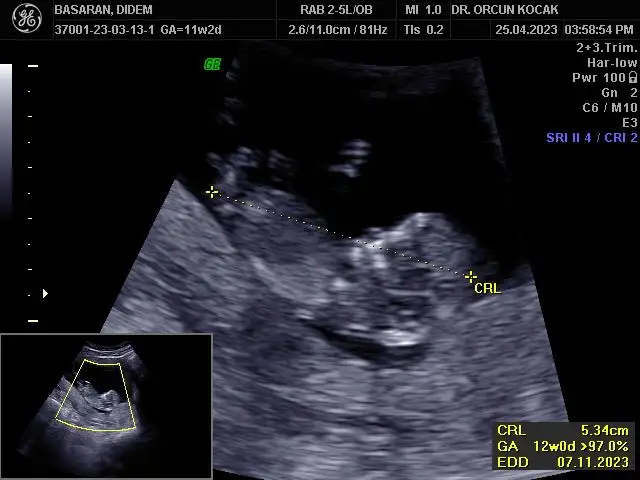

Merhabalar bende 11+5 im tahminlerinizi çok merak ediyorum kızlar sizce ne olabilirRamzi de nub’ u da erkek görünüyor canım

Bu ultrason görüntüsü mü yoksa alttan mı? Ultrasonsa benimkiyle aynı da kafatası bile. Ay ultrason yazmışsın zaten ya farketmedim. Sağlıkla kucağına al inşallah evinize neşe getirsin.Ultrason görüntüsü bugünün böyleydiben erkek hissediyordum bu sefer bulantım filan olunca ama değilmiş hiç teorilere bakmadım açıkçası o yüzden bilmiyorum